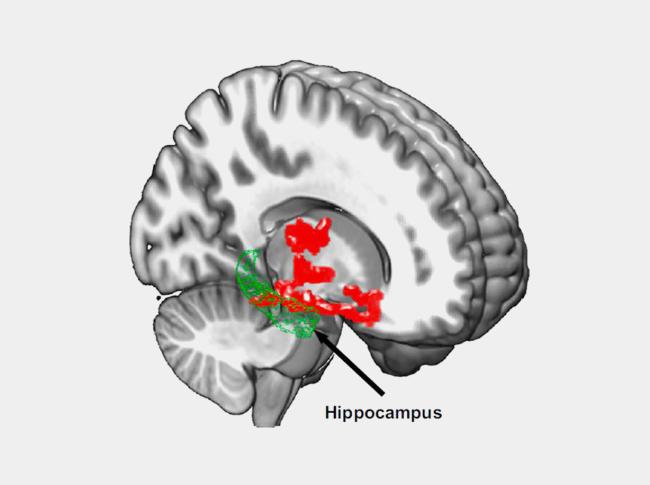

The researchers scanned participants’ brains after getting a full night’s rest and after a night of sleep deprivation (about 31 hours without sleep). Beta-amyloid increased about 5% in the participants’ brains after losing a night of sleep. These changes occurred in brain regions that included the thalamus and hippocampus, which are especially vulnerable to damage in the early stages of Alzheimer’s disease.

The scientists also found that study participants with larger increases in beta-amyloid reported worse mood after sleep deprivation. These findings support other studies that have found that the hippocampus and thalamus play a role in mood disorders.